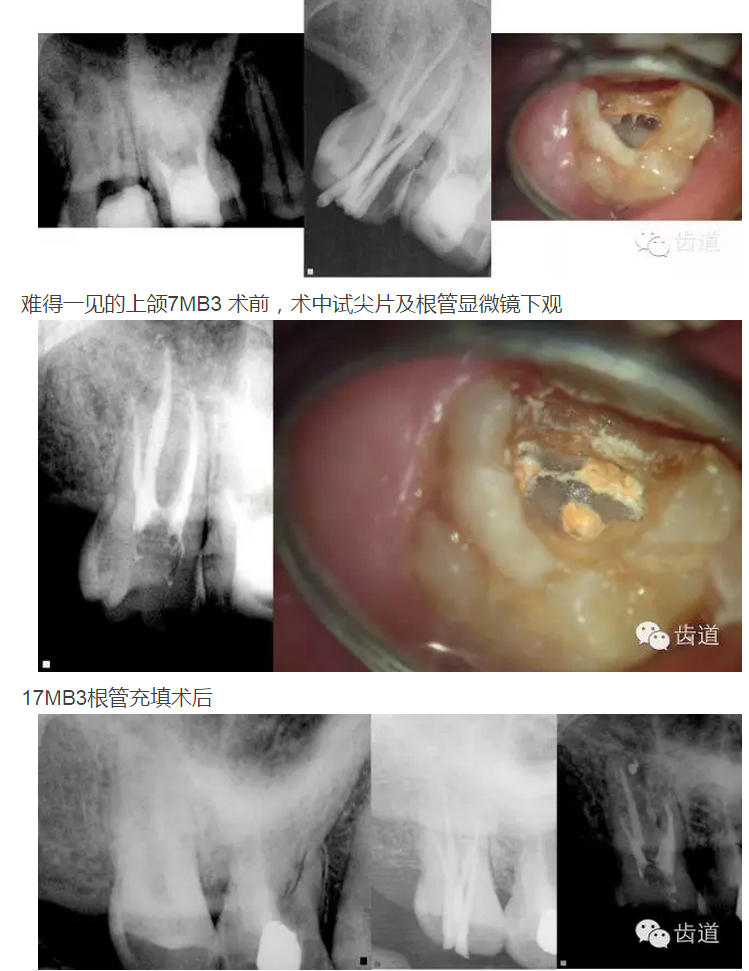

上頜第二磨牙:與上頜第一磨牙相似,多為3根管,偶見雙鄂根管;